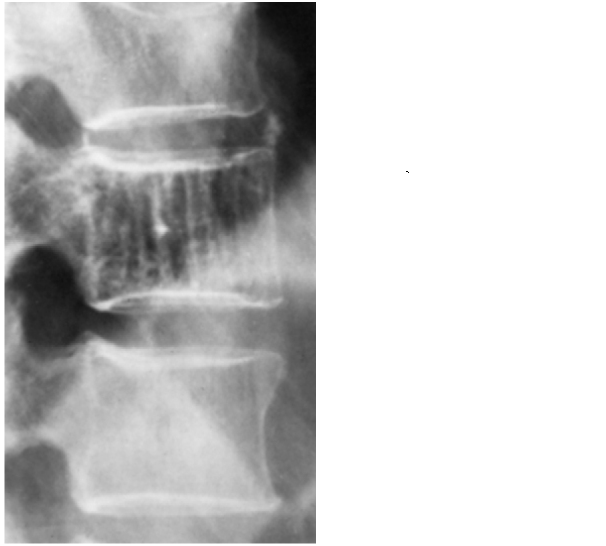

HEMANJİOM

Doktor Mehmet Subaşı

Toplumun yaklaşık % 10unda semptom vermeden omurga kemiklerinde yerleşmi...